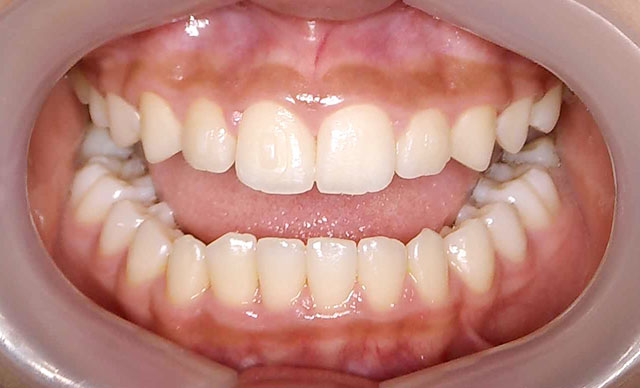

- case.7

術前

術後

症状:上下ガタガタ治療期間約10ヶ月